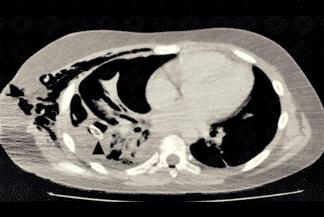

Descrição das figuras 3 e 4: Paciente portador da síndrome de Kartagener ( situs inversus e com bronquiectasias na base direita). Radiografia de tórax evidenciando hipertransparência no ápice do pulmão direito associado a não visualização da trama vascular, compatível com pneumotórax. No estudo em perfil, fica bem evidente o pneumotórax (seta vermelha).